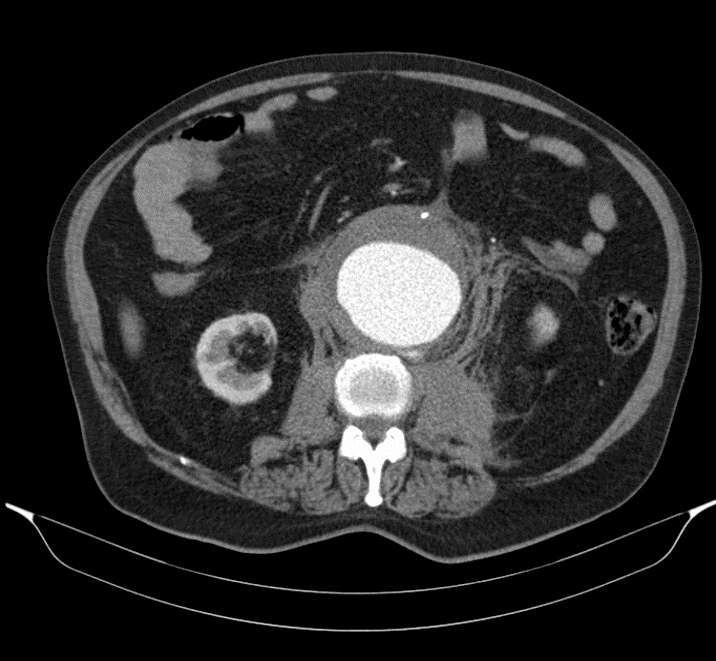

En caso de no haber hallazgos claros de patología abdominal que expliquen el dolor en la primera prueba realizada, que normalmente será una ecografía, se debe realizar una TC. Esta es la estrategia que más sensibilidad tiene, con menor dosis de radiación acumulada en el paciente [1]. Además, la TC es la prueba que más sensibilidad tiene en el abdomen [1]

En este caso se realiza una TC y no una ecografía porque la primera prueba de imagen ha dado hallazgos sugestivos de la patología que tiene el paciente y que causa el dolor. Como la TC es el paso lógico a dar en esta patología y la ecografía no aportará información añadida, no se pierde tiempo con ella.